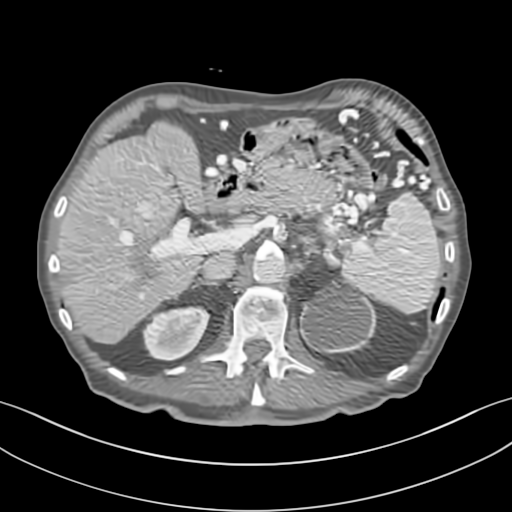

To demonstrate the effectiveness of the proposed network, we perform the qualitative comparisons over three representative abdominal images presented in Figs. 3, 5 and 7. For better evaluations of the image quality with different denoising models, zoomed regions-of-interest (ROIs) are marked by red rectangles and shown in Figs. 4, 6 and 8 respectively. Note that all results from different denoising models focus on two aspects: content restoration and noise-reduction. All CT images in axial view are displayed in the angiography window [-160, 240]HU.

The real NDCT images and corresponding LDCT images are presented in Figs. 3a and 3b. As observed, there are distinctions between ground truth (NDCT) images and LDCT images. Figs. 3a and 7a show the lesions/metastasis. Fig. 5a presents focal fatty sparing/focal fat. In Figs. 4a, 6a and 8a, these lesions can be clearly observed in NDCT images; in contrast, from Figs. 4b, 6b, and 8b, it can be seen that the original LDCT image is noisy, and lacks structural features for task-based clinical diagnosis. All adopted denoising models suppress noise to some extent.